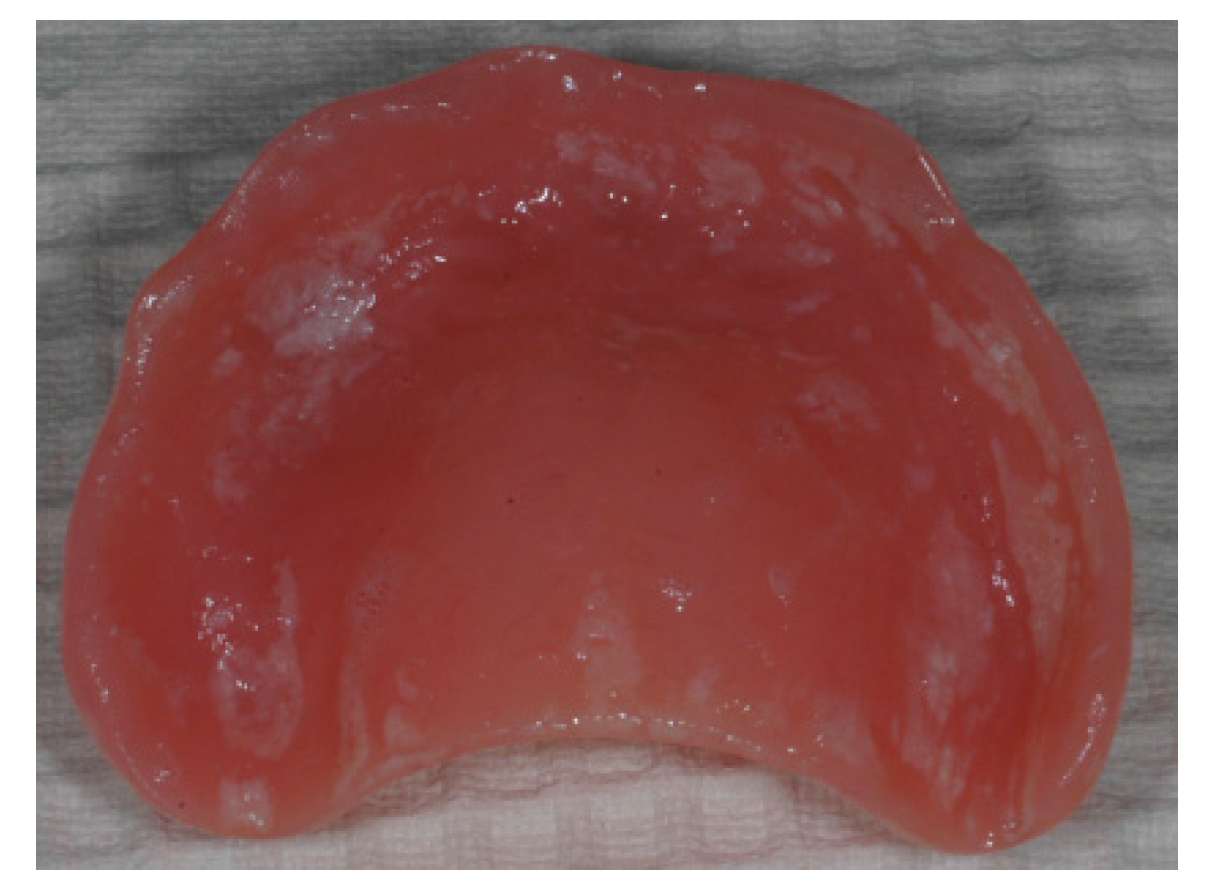

Figure 7. Different polymers have a different density and surface structure. The amount and size of pores and surface defects will affect the biofilm formation and composition. (A) polished heat cured acrylic; (B) unpolished cold cured acrylic; (C) polished polyamide (photo: Marit Øilo).

Polymers, such as resin based composites, glass ionomer and acrylics, have more pores and defects in the surface than metals, ceramics and enamel (Figure 7). Porosities will be filled with humidity and make perfect incubation chambers for certain microbes [14,24,47,48]. Biofilms on polymers develop quicker and will be more difficult to remove completely [41]. Acidic residues from the bacteria will roughen the surface, which will further complicate biofilm removal [15,16]. In order to achieve a surface roughness under the threshold value Ra = 0.2 µm on dental polymers special routines with stepwise polishing and finishing must be performed and repeated at regular intervals [38].